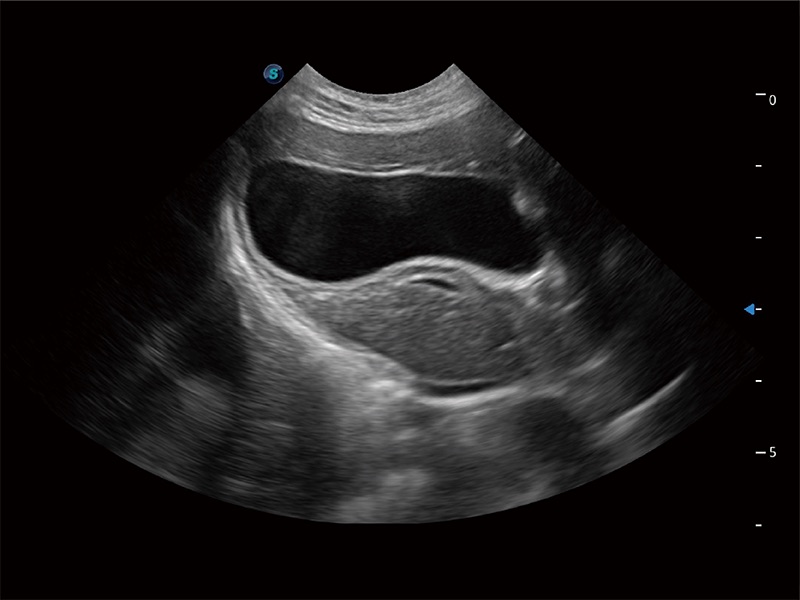

动物是人类最亲密的朋友和最值得信赖的伙伴。百老汇电子游戏官网也一直致力于探索动物专用的超声影像解决方案。全新推出的ProPet系列,是百老汇电子游戏官网在动物超声影像智能化、专业化、精准化的一次跨越式革新。动物不能用言语来表述自己的不适,通过超声影像,ProPet系列搭建了动物医生与不同物种沟通的“桥梁”,为动物医生注入了“治愈之力”。 ProPet 80 是百老汇电子游戏官网匠心打造的一款高端动物专用彩超,采用性能卓越的全新硬件架构,极大提升超声系统的运行效率和数据处理能力,帮助动物医生从容应对日益增多的挑战性病例和日益多样化的临床需求。

高性能和先进的临床应用工具可以为动物医生提供临床信心。ProPet 80 搭载了先进的腹部和浅表应用工具,帮助医生在日常临床实践中发挥前所未有的作用。

ProPet 80 全新的动物超声智能软件和丰富的探头群,为动物医生提供了高清晰度和精细分辨率的图像,无论在宠物、马科、畜牧还是实验室动物等应用中都可以轻松应对,为您的日常工作带来满意的体验。